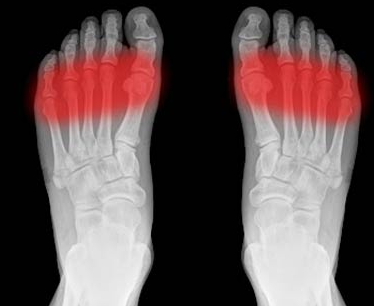

Kubis Napisano 31 Stycznia 2024 Udostępnij Napisano 31 Stycznia 2024 (edytowane) Może głupi pomysł, ale masz jeszcze oryginalne wkładki do tych butów? Wyciągasz Sidasa wkładasz oryginalne i sprawdzasz. Jeśli nie to, to nie jest to problem samej wkładki tylko objęcia stopy skorupą. Sprawdziłbym co się dzieje z poluzowaną (całkowicie) ostatnią klamrą która zwęża skorupę podobnie do jej dociskania od góry. Ew. druga klamra o ząbek mniej. Jeśli problem mija - prawdopodobnie skorupa jest tak ciasna bocznie, że robi się ucisk na nerwy i naczynia krwionośne pomiędzy stawami, który odbierasz jako ból wynikający z nacisku "od spodu" lub "od góry". Ale zawsze możesz sprawdzić ile miejsca od spodu i od góry masz w skorupie wkładając tam nogę bez kapcia. Będzie widać dokładnie, czy więcej miejsca jest góra/dół czy prawo/lewo. Sprawdź jak ilość miejsca zmienia się gdy klamry masz dopięte do jazdy, lub poluzowane (gdzie tego miejsca ubywa szybciej przy dopinaniu - od góry czy od boku). edit: Inną możliwością jest ból spowodowany złą dystrybucją obciążenia stopy. Są osoby, które mają wysokie podbicie i niską ruchliwość w kostce (w kierunku przód tył). Dokładanie klina za łydkę (spodziewam się że w twardych butach może taki klin być, zwłaszcza wykorzystywany przez osoby o szczupłych łydkach posiadające sportowe buty z regulacją za łydką) powoduje zwiększony docisk w obszarze śródstopia (forefoot) - dokładnie tu: Takie kilka pomysłów na zlokalizowanie przyczyny. Edytowane 31 Stycznia 2024 przez Kubis 1 Cytuj Odnośnik do komentarza Udostępnij na innych stronach More sharing options...